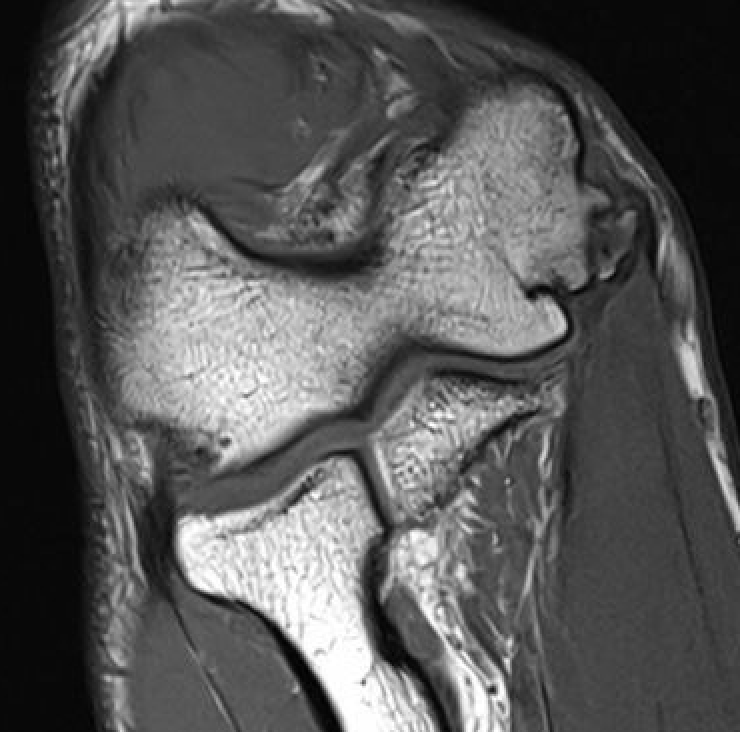

MRI

Intact

MRI findings in asymptomatic throwing elbows

- MRI of elbow in 426 baseball players

- 2/3 asymptomatic, 1/3 symptomatic

- 30% had evidence of high grade UCL injury

- no difference between groups